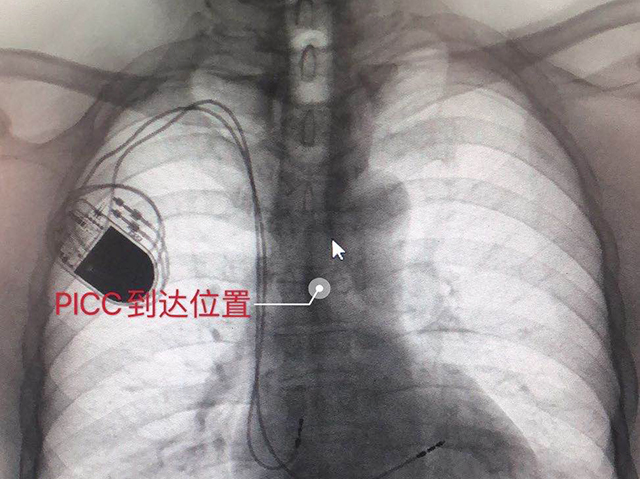

经心内科会诊医生、主管医生卢英、护士长张钟群、技术员许国彬及静疗小组成员(彭旭、沈蒋永琰、王磊、梁菊、蒋华艳)集体讨论后,敲定了最终方案:①选择置管深度(导管末端)到达第5胸椎间隙水平,这样既可以保证顺利穿刺后用药安全(不容易管道异位),又减少了置管后并发症的出现,留置时间也可达八个月以上;②操作中使用血管B超机探查血管位置进行穿刺并置入导管;③采用多功能心电监护仪,确定导管置入深度准确,保证在置管过程中可看到起搏器正常工作(在监护仪波形上可出现起搏丁);④置管完成后利用我科独有的定位模拟机影像技术,可直观地看到PICC管道经过的每一个位置,是否接触起搏器电极线。

经过充分准备,放疗科团队通力合作,成功为患者经左侧上臂外周静脉血管置入中心静脉导管,解决了长期输液难题。